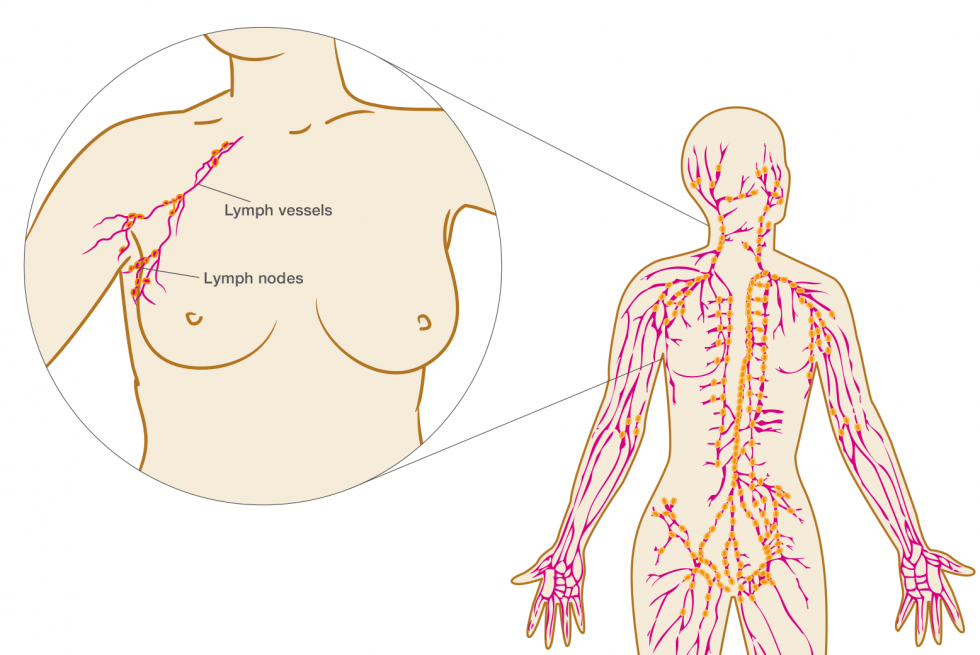

Изображения и схемы: как выглядит лимфа